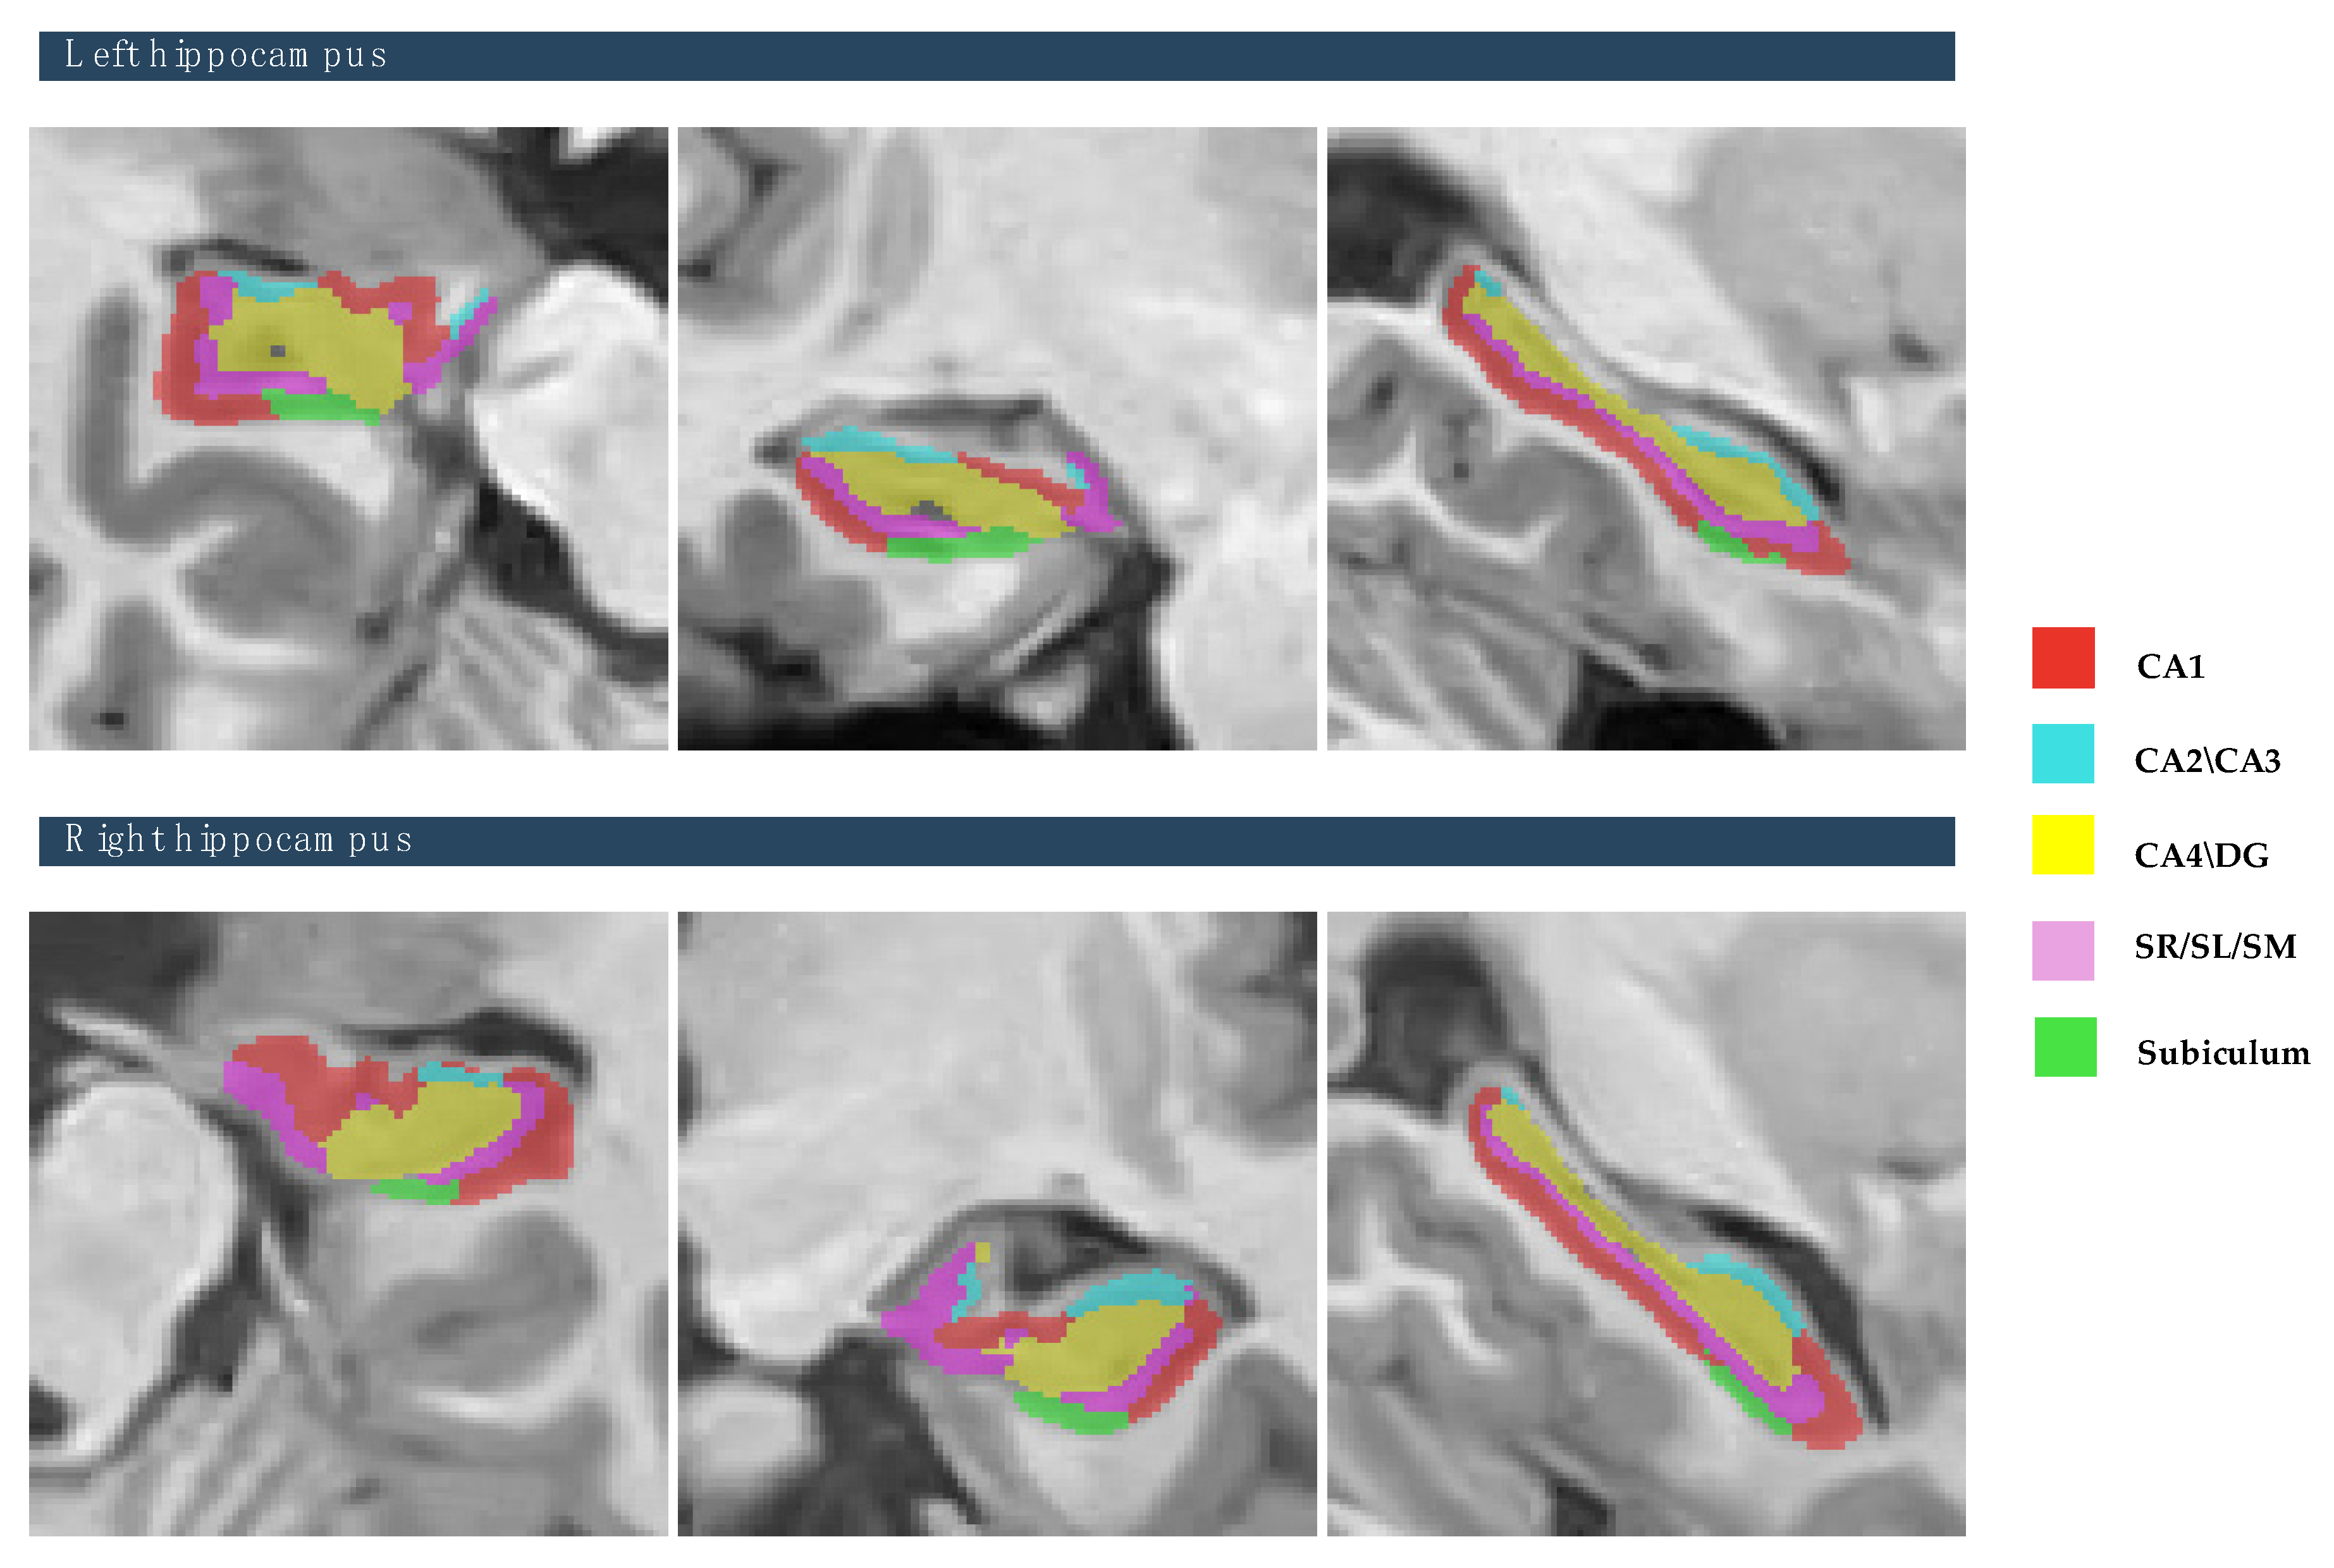

The raw data of MR brain images were analyzed using volBrain Online software that is an automated and online MRI brain volumetry system (https://volbrain.net/, accessed on 1 December 2024). AssemblyNet, VolBrain and HIPS-monospectral pipelines were used to assess brain tissue, subcortical structures and hippocampal subfields, respectively. The high resolution T1-weighted imaging volumes underwent standard pre-processing steps: denoising, coarse inhomogenity correction, MNI space registration, fine inhomogenity correction and intensity normalization. Then, the segmentation process was applied, which consists of the following steps: spatially adaptive non-local means denoising, rough inhomogeneity correction, affining registration to MNI space, fine SPM-based inhomogeneity correction, intensity normalization, non-local Intracranial Cavity Extraction (NICE), tissue classification, non-local hemisphere segmentation (NABS) and non-local subcortical structure segmentation, as depicted in Figure 1.

The study focused on eight subcortical structures, divided into right and left hemispheres: the putamen, caudate, pallidum, thalamus, hippocampus, amygdala, and nucleus accumbens, and lateral ventricles, as depicted in Figure 2. Also, this study focused on the five hippocampal subfields, divided into right and left hemispheres: cornu ammonis 1 (CA1), cornu ammonis 2 and 3 (CA2–CA3), cornu ammonis 4 and the granule cell layer of dentate gyrus (CA4-DG), the strata radiatum/lacunosum/moleculare (SR-SL-SM), and Subiculum, as depicted in Figure 3. The volumetric measurements of the global tissue estimation (GM, WM, and CSF), macrostructures (cerebrum, cerebellum, vermis, and brainstem), subcortical structures (putamen, caudate, pallidum, thalamus, hippocampus, amygdala, nucleus accumbens, and lateral ventricles), hippocampal subfields (cornu ammonis 1 (CA1), cornu ammonis 2 and 3 (CA2–CA3), cornu ammonis 4, and the granule cell layer of dentate gyrus (CA4-DG), strataum radiatum/lacunosum/moleculare (SR-SL-SM) and Subiculum) were extracted.

Figure 3. The process of hippocampal subfields segmentation based on the Winterburn atlas. Right panel shows the color coded of hippocampal subfields that are overlaid onto the subject’s high-resolution T1-weighted anatomical scan [subject 10].